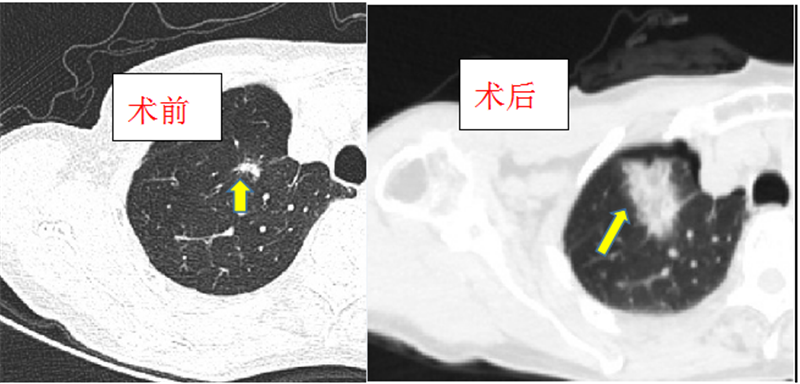

患者王某69岁,右肺癌术后六年。1月前,在市一院CT检查时发现肺内部分结节增大,变实。由于常规化疗、靶向、免疫治疗等存在多方困难,经多学科MDT讨论后决定,邀请昆明市延安医院张培先教授到我院进行手术指导,由肿瘤科张超主任及其团队对变化较大的两个结节给予“消融治疗”。仅8分钟,两个肺结节完全被灭活。术后,患者病情平稳,稍作休息后便可下床行走。

微波消融适用于:1.无法通过手术切除的肿瘤;2.因年龄、心脏、肝脏等原因不能进行较大手术切除的原发性肿瘤例如肝部、肺部的实性肿瘤;3.姑息性治疗,患者病情严重,肿瘤瘤体大且个数多,其他治疗手段效果不明显的情况下,可选用微波消融来减少肿瘤以延长患者的生命。该技术是在CT精确引导下,用微波消融针穿刺进入肿瘤内,利用它释放的微波磁场使周围的分子高速旋转运动并摩擦升温,使癌组织局部在几分钟内达到100℃以上的温度,引起肿瘤靶组织发生凝固性坏死,而周围组织极少或不受损伤,达到“烧死”肿瘤细胞的目的。